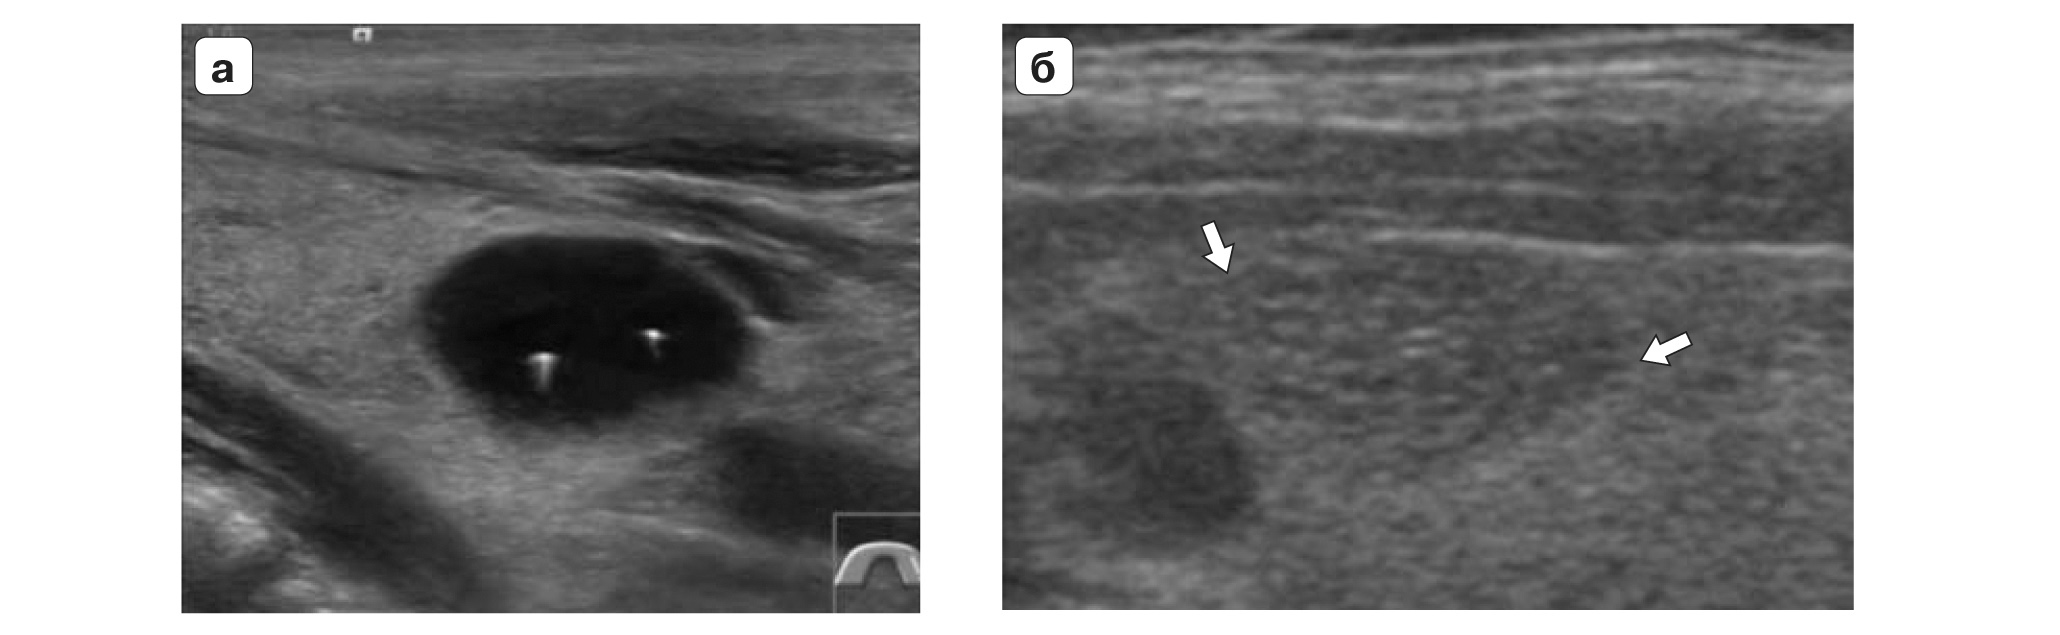

TI-RADS 4. Узлы более 1,0 см в диаметре с “малыми” признаками злокачественности для выполнения ПУНКЦИИ (рис. 3):

- солидные узлы, равномерно или неравномерно умеренно пониженной эхогенности;

- солидные узлы изо- или гиперэхогенные, имеющие “малые” признаки злокачественности:

– гипоэхогенные включения;

– округлая/шаровидная форма;

– неравномерно утолщенное хало;

– макрокальцинаты.

Рис. 3. TI-RADS 4: а – узел шаровидной формы, с ровными и четкими контурами, умеренно пониженной эхогенности, с участками более низкого эхо, с макрокальцинатом. Узел окружен тонким хало (фолликулярная неоплазия); б, в, г (поперечное и продольное сканирование левой доли ЩЖ) – изоэхогенные узлы с гипоэхогенными включениями, с четкими контурами, с тонким хало (фолликулярная аденома); д – изоэхогенный узел с гипоэхогенными включениями, с неравномерно утолщенным хало (фолликулярный рак).